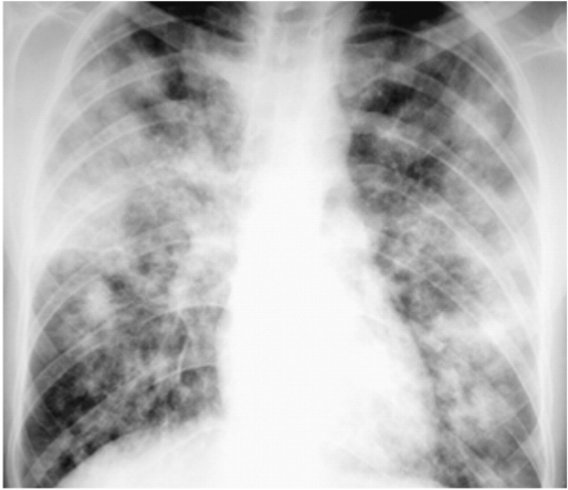

This is multifocal pneumonia, which _____ DPLD

This is multifocal pneumonia, which is not DPLD